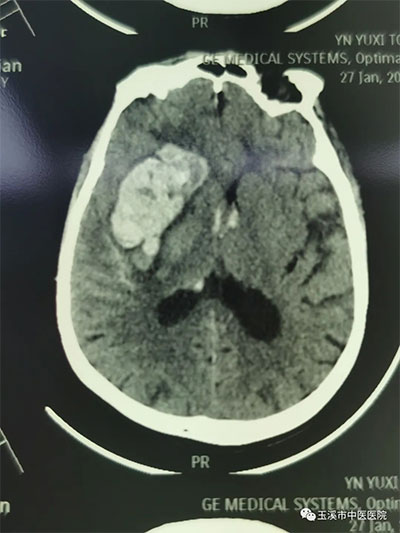

手術(shù)前顱腦CT提示:右側(cè)島葉、右側(cè)基底節(jié)區(qū)腦出血出血量估算大約50ML,部分血液破入側(cè)腦室。